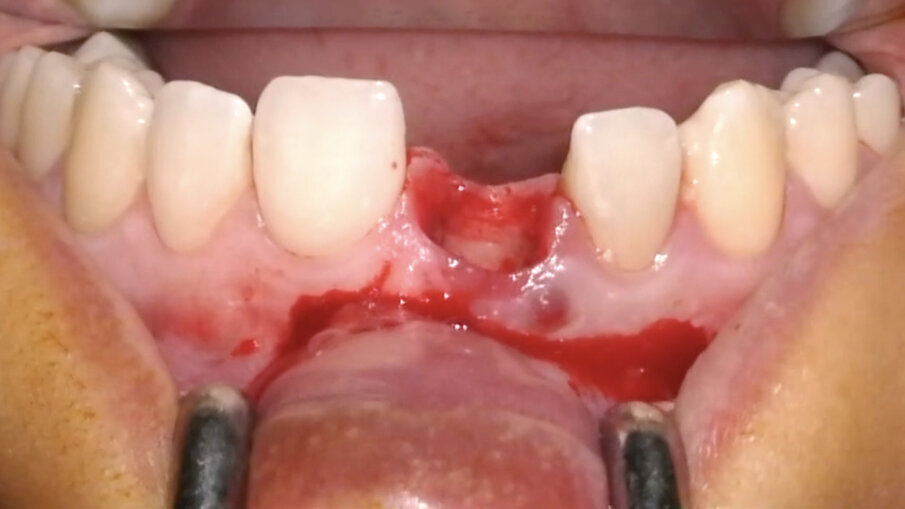

Non vanno eseguite incisioni di scarico in quanto non sono necessarie (Fig. 13). Diversamente, nei casi di edentulia parziale frontale deve essere eseguita un’incisione vestibolare (Fig. 14) a partenza intra-sulculare dai denti adiacenti. Come noto, tale incisione non deve coinvolgere la parte coronale delle papille: l’interessamento dei picchi ossei, infatti, porterebbe inevitabilmente alla perdita di 1-1,5 mm di osso con compromissione dell’estetica finale. In entrambi i casi, al fine di posizionare una matrice in collagene, verrà eseguita un’incisione a spessore parziale creando una piccola tasca mucosa corrispondente alla porzione buccale della zona trattata (Fig. 15).

Fig. 11_Estrazione del dente 1.1.

Fig. 12_Dente 1.1 estratto.

Fig. 13_Alveolo integro e tessuti molli non incisi.

Fig. 14_Disegno del lembo nei casi di edentulia parziale frontale.

Fig. 15_Incisione verticale per la creazione della tasca mucosa a spessore parziale.